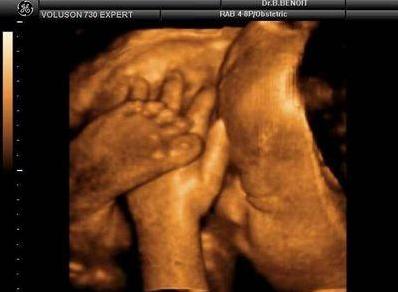

【在妇产科医院,你可以看到这样的胎宝】

霍霍,打拳啦~